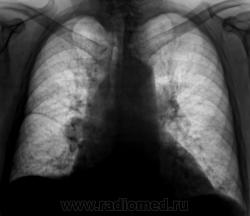

Контроль после флюорографии.

При расшифровке флюорограмм пациент "взят на контроль". Произведено стандартное дообследование.

Ваше мнение коллеги?

Произведены томограммы.

Здравствуйте Almo! Томограммы выполнены в стандартных срезах - 7, 9, 11 см.

Эта штучка неотделима от правой промежуточной артерии...

Вот раздумываю послать на КТ или не посылать. Пациент ничего и слышать не хочет о поездке в областной центр.

На "томо" шикарно видно:

1. Гиповентиляцию правого лёгкого.